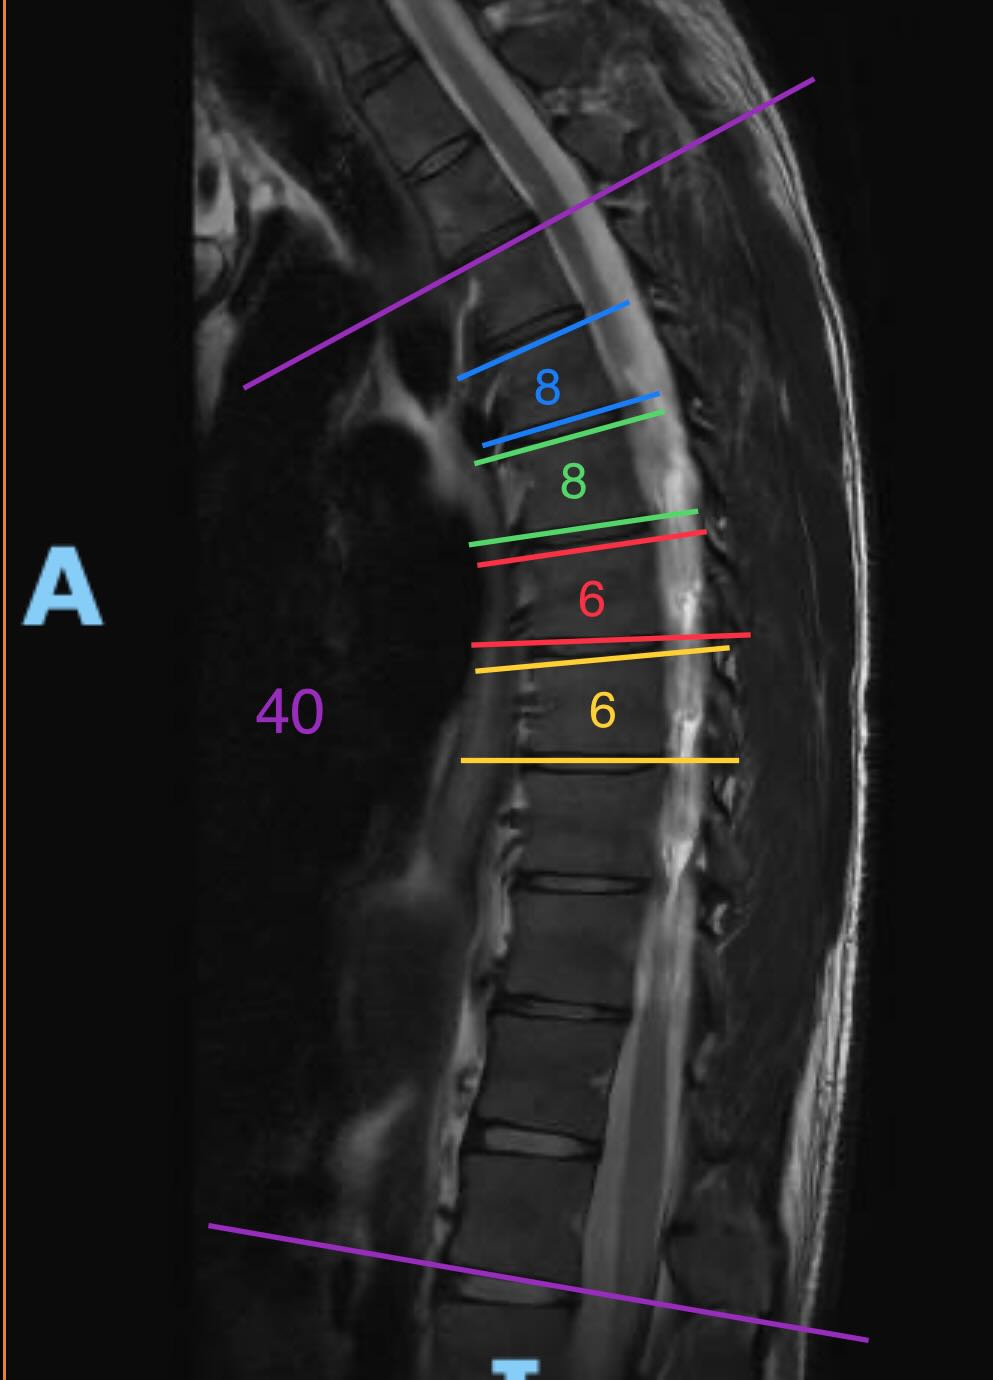

Die Bilder (Winkel von mir eingezeichnet und gemessen):

Ich habe keine Ahnung was mit Irregularitäten gemeint ist. Eine Grad-Zahl der Kyphose wurde auch keine genannt.Es zeigen sich tatsächlich mindestens drei Wirbelkörper leicht keilwirbelförmig konfiguriert (Cobb-Winkel >5 Grad), dies ist ein diagnostisches Kriterium des Morbus Scheuermann. Allerdings fehlen die für den Morbus Scheuermann typischen anterior betonten Irregularitäten respektive sind nur sehr diskret ausgebildet. Somit kann weder eindeutig die Diagnose eines Morbus Scheuermann gestellt werden noch kann dieser ausgeschlossen werden.

- Ist das anhand des Bildes eine leichte/mittlere/stärkere Hyperkyphose?